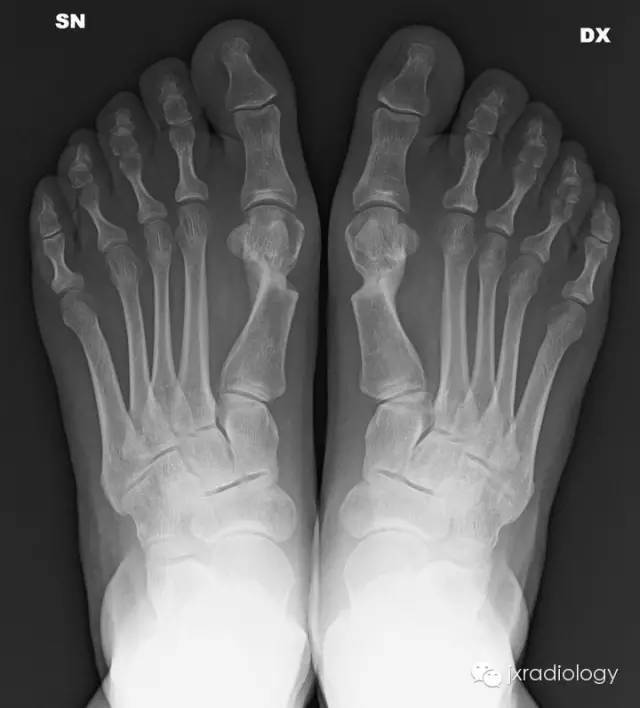

踇外翻畸形(Hallus valgus)

踇外翻(Hallus valgus)

是足部常见疾病,通常双侧发病,随着年龄增加,踇外翻患病率有增加趋势,65岁老年人患病率为12% ~56%,女性多发, 男∶女为 1∶15 ~ 1∶19value币。踇外翻的发生发展与先天性因素和后天性因素具有密切的相关性,其中遗传因素最为明确,调查显示50% ~90%的患者有家族遗传史,为常染色体显性遗传。

△ 常用测量角

常用测量角:

1、跖间角 (Intermetatarsal Angle, IMA) value币,第1、2跖骨纵轴延长线之夹角,正常6°~11°,正常 < 9°;

2、踇外翻角(Hallux Valgus Angle,HVA;又称 Hallux abductus angle,HAA)第1跖骨纵轴线与第1趾近节趾骨纵轴线之夹角,正常 < 20°value币。

踇外翻分度:

根据跖间角 (IMA)踇外翻角(HAA)的大小将其分为:

轻度(HAA:15°~30°;IMA≤13°);

中度(HAA:30°~40°;IMA:13°~16°);

重度(HAA≥40°;IMA≥16°)value币。